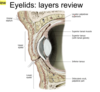

What are the layers of the eyelids?

- Thin skin

- obicularis oculi

- palpebral part

- orbital septum (Periosteum to tarsi)

- tarsus

What muscle is indicated?

What is its function?

Attachment?

Innervation?

Levator palpebrae superioris (LPS)

- What is its function?

- elevates upper eyelid

- Attachment?

- Innervation?

- cranial never III

What muscle is indicated by the photo?

What is its function?

Attachment?

Innervation?

Superior tarsal

- What is its function?

- helps keep eyelid open (helps LPS)

- Attachment?

- origin: LPS

- Innervation?

- smooth muscle

- sympathetic

What are the squiggly lines indicated it the photo?

Tarsal glands